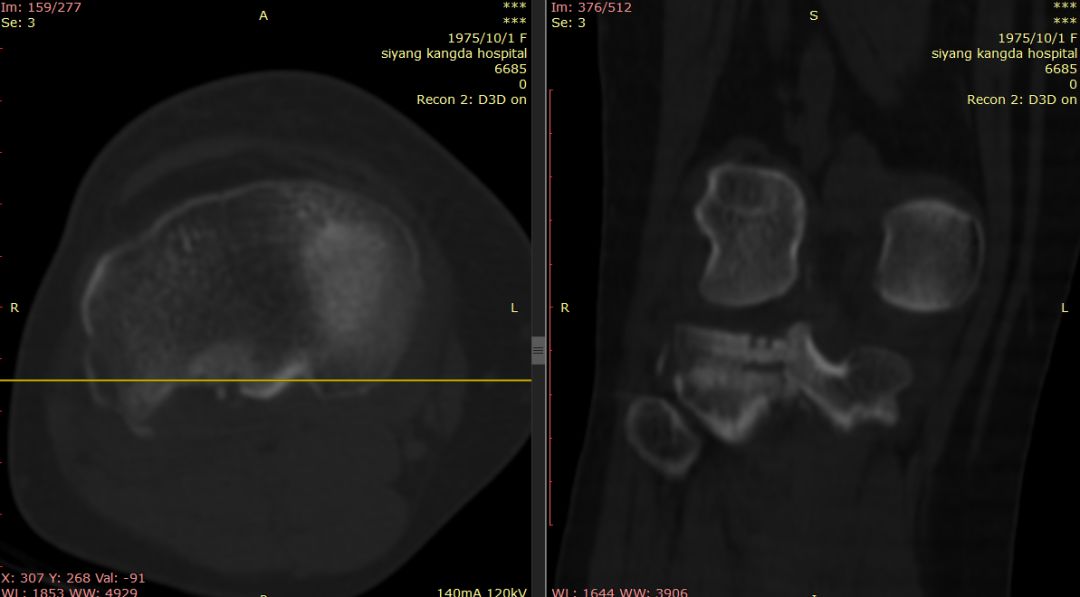

女44岁,外伤

Segond骨折,因下肢过度内翻、内翻暴力所致胫骨平台外侧缘的撕脱性骨折。撕脱的骨折块较小,小骨片多位于腓骨头上方,且较少波及关节面而易被忽视。往往合并前交叉韧带损伤、半月板损伤及外侧副韧带损伤。

有文献报道,Segond 骨折合并有前交叉韧带(ACL)损伤的发生概率约为75%~100%,若没有得到及时处理,关节将会出现反复扭伤的现象,容易引发膝关节继发性损害,最终将导致关节过早的出现退变和骨关节病的发生。当怀疑Segond骨折,应该做MRI检查,评价膝关节组织损伤情况。